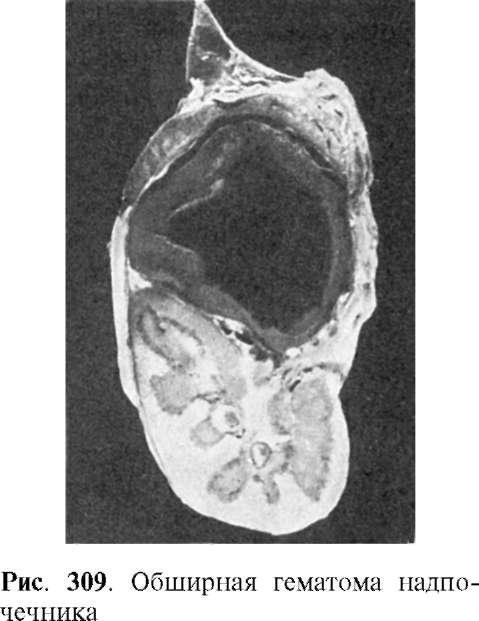

Кровоизлияния в надпочечникивстречаются реже, бывают преимущественно односторонними, в танатогенезе имеют значение двусторонние кровоизлияния, которые связаны скорее не с родовой травмой, а с гипоксией. Иногда наблюдаются обширные гематомы с разрушением надпочечника (рис. 309). В исходе образуется киста или организация гематомы с кальцинозом и ожелезнением, редко встречается нагноение.